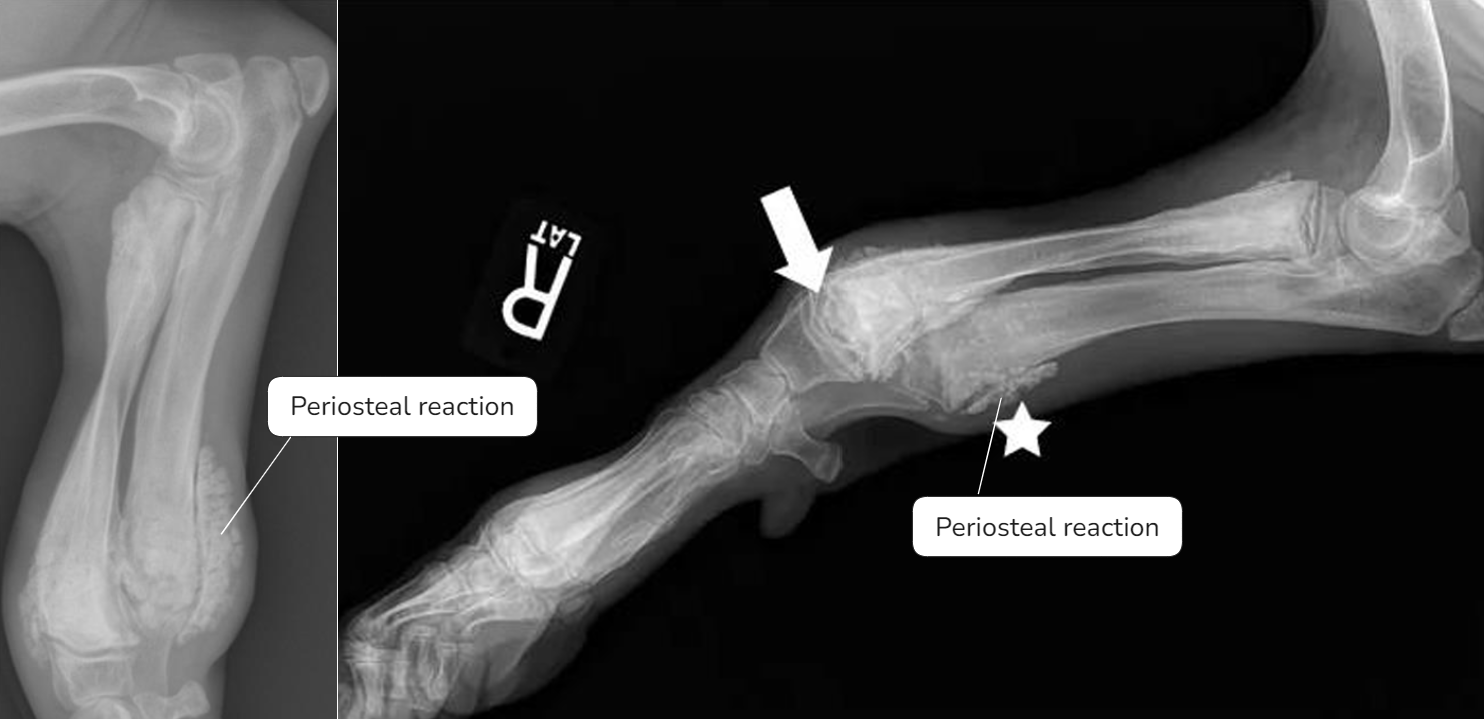

| - 아래쪽만 양옆으로 커지면서 flaring 양상을 보임. | Early sign - Metaphyseal soft tissue swelling | 비정상적인 periosteal reaction이 심하게 나타남, 성장판도 손상 받음 |

- Physeal line의 손상이 심해 각기형? 등 문제가 될 수 있음.